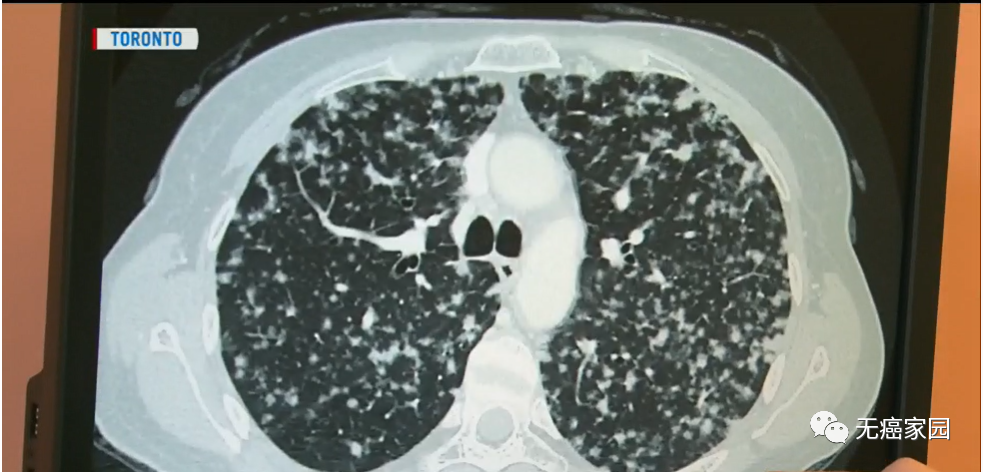

就在她接受一系列治疗的2年后,得到了更加毁灭性的消息:癌症已经扩散到她的另外一个肺部,无法进行手术治疗,她的病情也好似画上了休止符。

以塞拉托为例,她每天只服用两片劳拉替尼的靶向药进行治疗。之所以能够服用这种抗癌新药,全都源于她的肿瘤发生了ALK(间变性淋巴瘤激酶)基因突变,这种突变会发生在3%~5%的肺癌病例中。

虽然生活方式很奇怪,需要每三周进行一次体检,甚至每隔一周扫描一次,但是7年后,她的生活状态很好,达到了与肺癌共存!她正在考虑重返工作岗位。她与其他被诊断出患有肺癌的患者交谈,并结识了她的伴侣帕特里克并与之结婚。